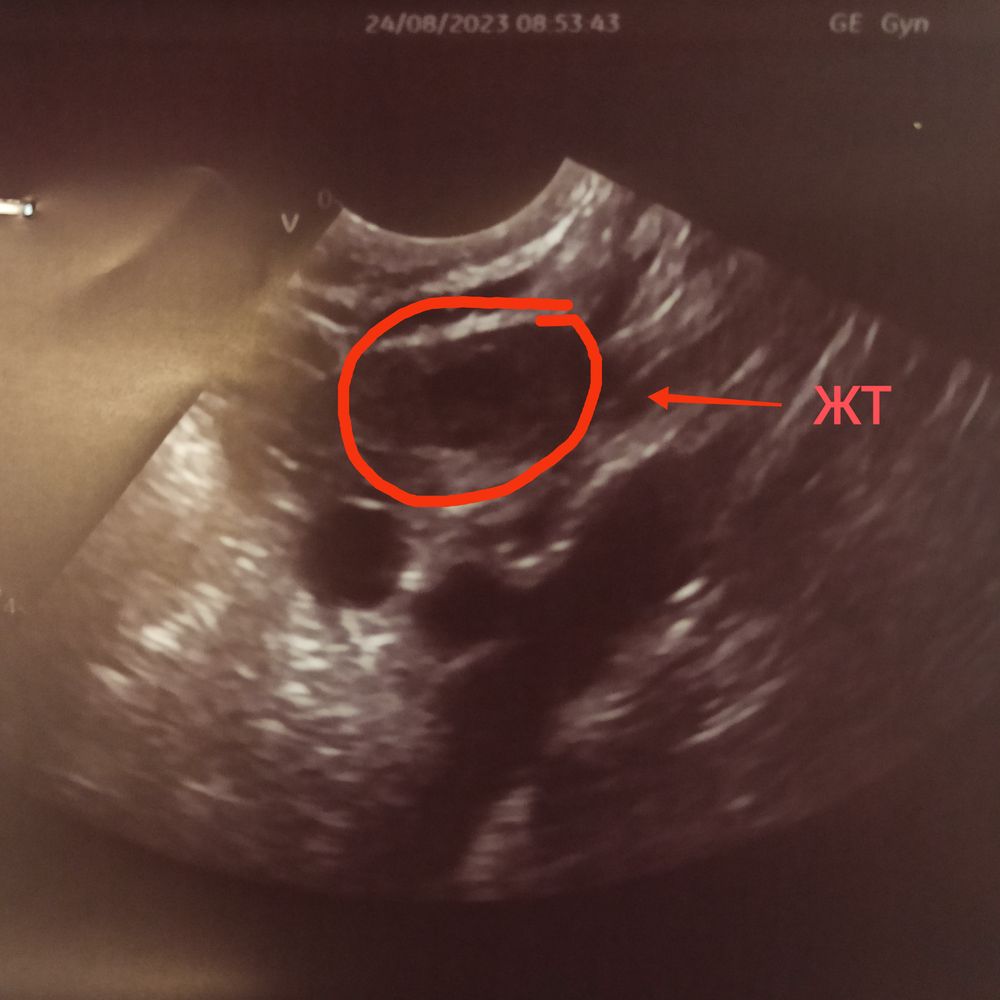

7 дпо ЖТ...

Не могла успокоится и решила сходить к другому врачу на УЗИ:

эндометрий 10 мм,

в ПЯ ЖТ 10 мм,

свободная жидкость 10 мл.

Так что с таким маленьким ЖТ беременость маловероятна, но я на Утрожестане, может из-за него ЖТ расслабилось и не растёт.